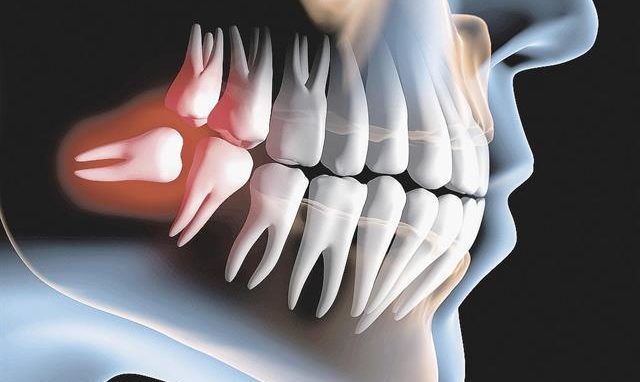

A cirurgia de terceiro molar, popularmente conhecida como extração do siso, é um procedimento necessário para muitos pacientes que enfrentam desconfortos ou complicações.

A escolha da melhor opção de tratamento é fundamental, e o Dr. Marcelo Oleiro se empenha em garantir que cada paciente receba a atenção e os cuidados necessários. Os benefícios da cirurgia incluem a prevenção de infecções, a melhoria do alinhamento dental e a redução da dor, proporcionando uma experiência positiva e um retorno à qualidade de vida com segurança.